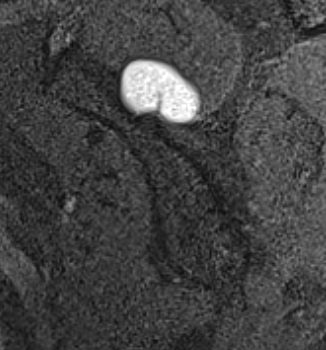

MRI

Spinoglenoid cyst

Spinoglenoid cyst with SLAP tear and posterosuperior labral tear